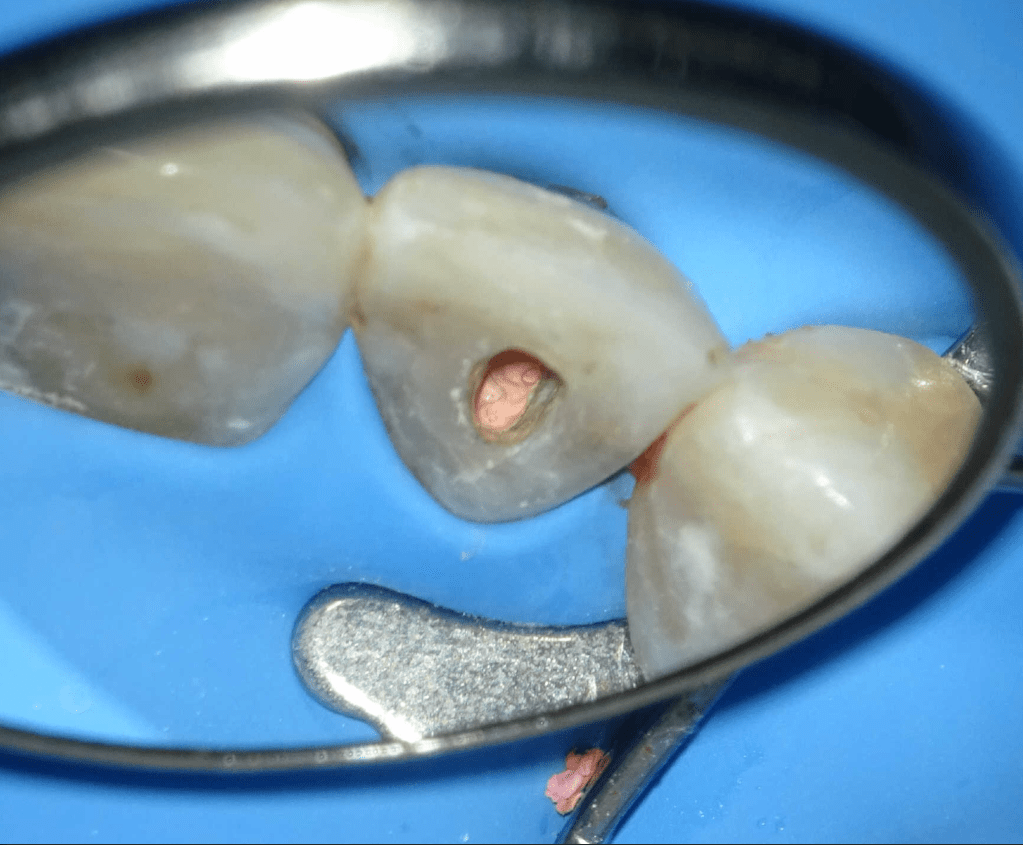

Pulpotomía biodentine + reco preendio